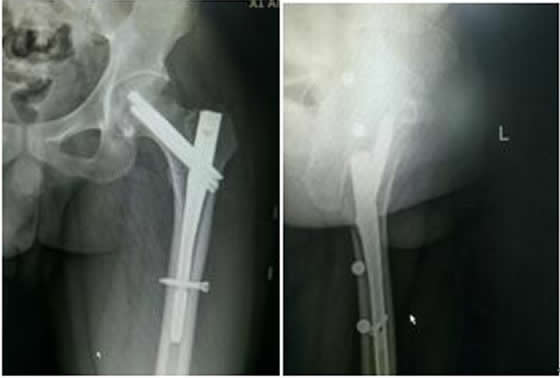

患者稅某某,男,26歲,以“外傷致左髖疼痛、活動(dòng)受限2小時(shí)余”之主訴入院,入院診斷:左股骨近端骨折(A1)?;颊哂?016.9.19在硬腰聯(lián)合麻醉下行骨折閉合復(fù)位InterTan內(nèi)固定術(shù)。手術(shù)順利,術(shù)后患者恢復(fù)良好,現(xiàn)已出院。術(shù)后復(fù)查拍片如下:

左髖關(guān)節(jié)正側(cè)位X線(xiàn)片